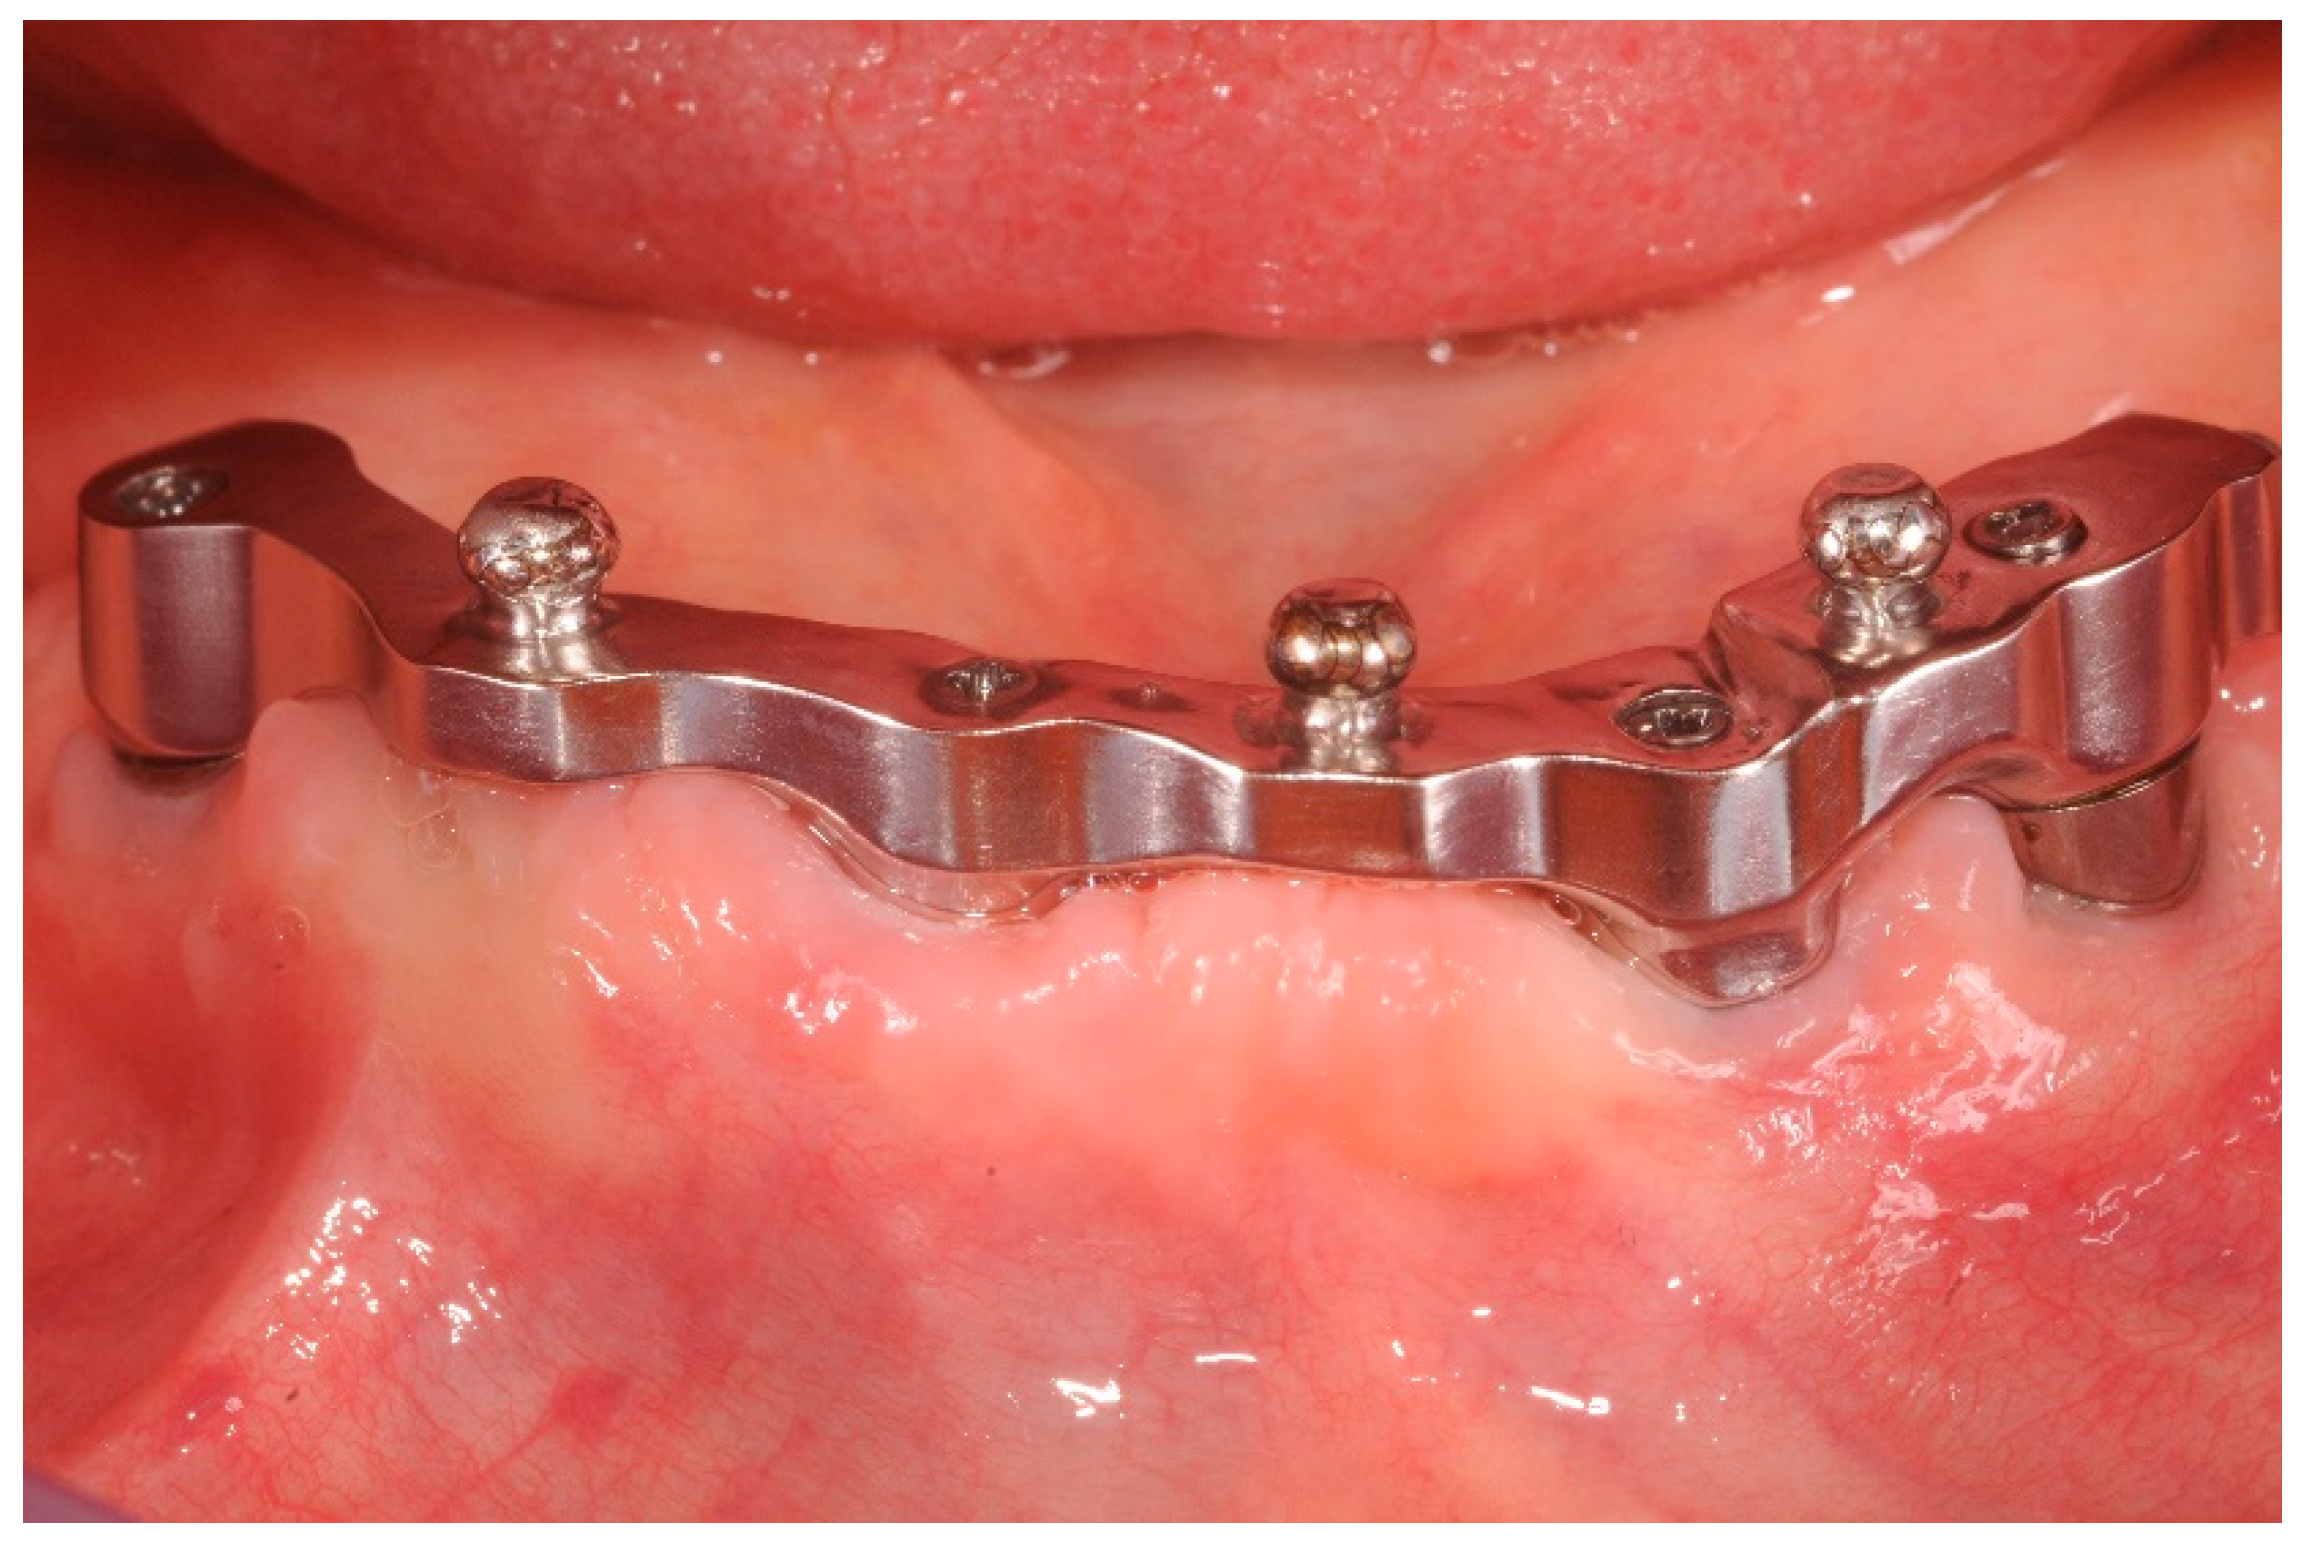

Figure 3.

CAD/CAM implant-bar and the metal counterpart, front view at three years follow up.